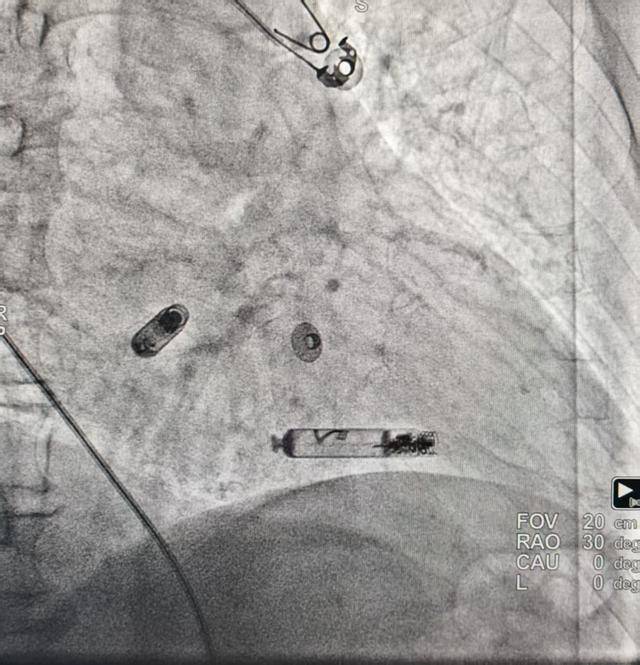

江斌主任介绍说:“这种起搏器没有导线(无线)、无需胸部切口、无体外装置,大大避免了患者创伤与潜在并发症。这是双腔的起搏器,以往的无导线起搏器只能起搏心室,不能实现房室同步。而新一代双腔无导线起搏系统就像给心脏带了一对‘蓝牙耳机’,一个驻守心房,一个驻守心室,它们之间能够‘无线对话’,协同工作,真正模拟人体自然心跳的房室顺序收缩。”

完善相关术前准备,手术由心血管内科蒲晓群教授、江斌主任共同操作。术中经患者大腿根(股静脉)这一微创路径,通过造影确认,精准将心室无导线起搏器植入右心室低位间隔,再将心房无导线起搏器通过递送导管置入右心耳基底部,张力测试后顺利释放。术后患者各项指标良好,i2i通讯流畅,房室同步性表现优异。